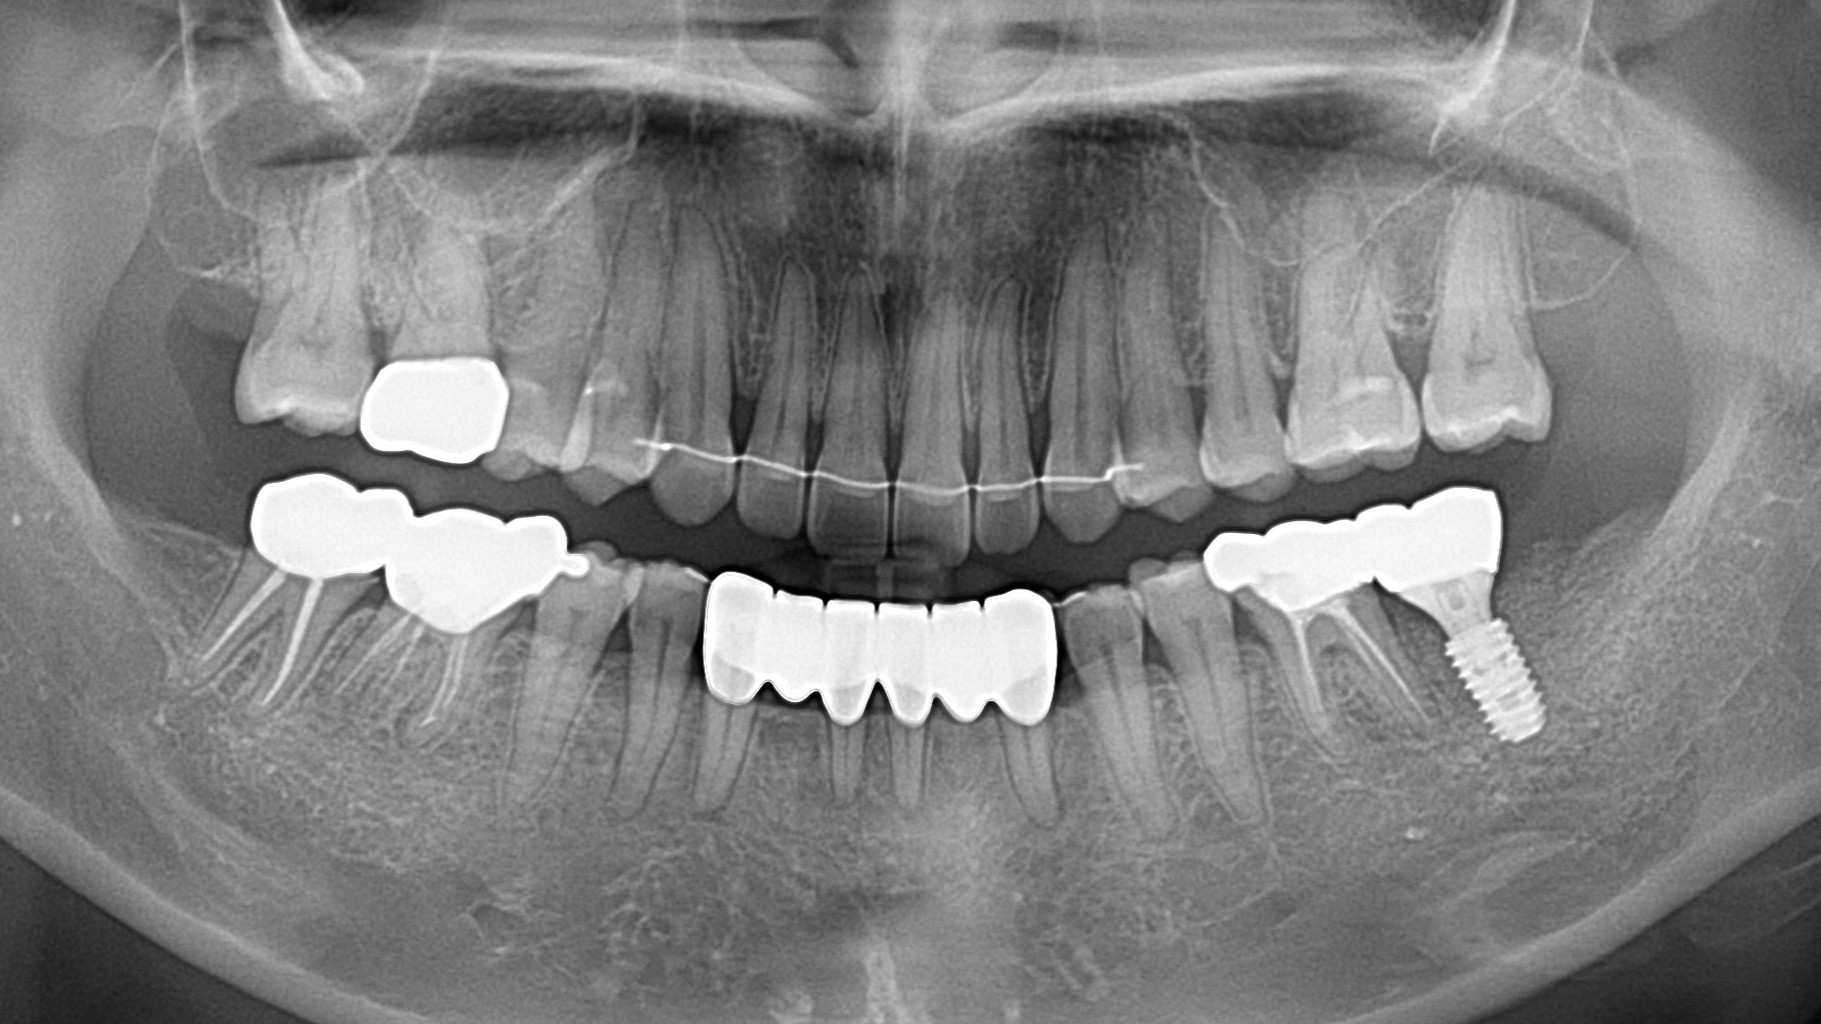

임플란트

하악 임플란트 케이스

성명: 박** 님

치료기간: 임플란트 4개월

치료전: 2025.07.03 ― 치료후: 2025.11.07

동일인이고 저희 병원에서 치료받으신 고객입니다. 동일조건으로 촬영되었고 별도의 조작이 없는 전후사진입니다.